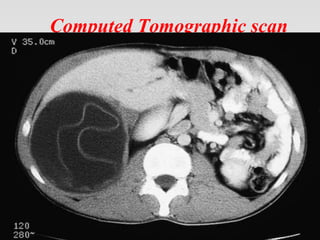

Computed Tomographic scan

Diagnostic Studies • LaboratoryTests • Imaging – X-ray – USG – CT – MRI – Nuclear Scan • Other Tests

IMAGING TECHNIQUES • PlainX-RAY Films: • Findings from plain films of the chest, abdomen, or any other involved site are nonspecific and mostly non revealing. A thin rim of calcification delineating a cyst is suggestive of an echinococcal cyst.